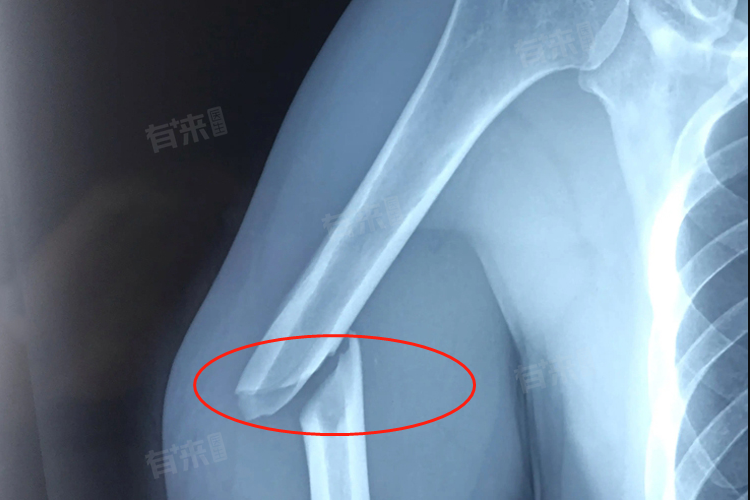

如果是简单的右肱骨骨折,骨折断端移位不明显,经过妥善的复位,一般在4-6周初步愈合,在这个期间,骨折断端开始形成骨痂,连接骨折部位,如果是粉碎性骨折,愈合时间会显著延长,可能需要8-12周甚至更长时间才能初步愈合,因为粉碎性骨折的断端较多,骨痂形成和连接的过程更为复杂。